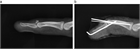

1. 骨折する部位により特徴的な変形を呈する。

1. 関節拘縮を起こさないような内固定と外固定が必要であり、解剖の熟知が重要である。